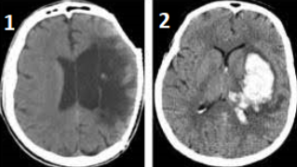

Imagem de tomografia computadorizada

- AVC isquêmico

- AVC hemorrágico